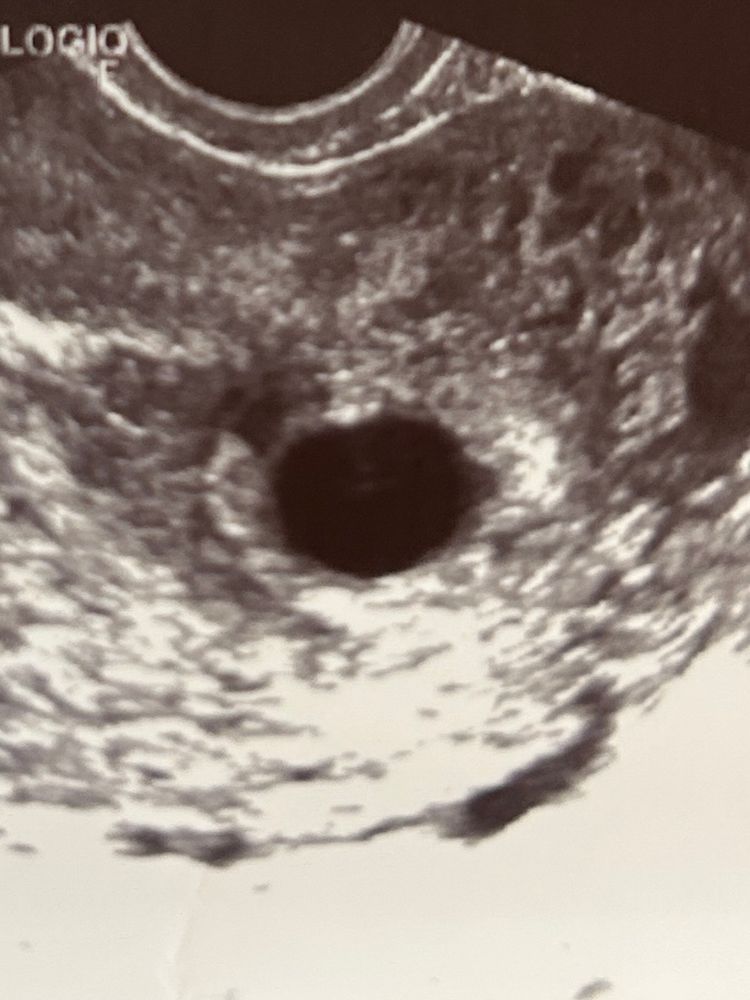

Изображение ну вот если осветлить я вижу- и даже если не осветлить видно, но сугубо моё личное дело, перепроверить!!!! а недоврачей у нас к сожалению пруд пруди.

Татьяна, смущает, что и желточного мешочка даже нет

Там как будто что-то мерцает в серединке ПЯ, такое белое облачко. Вон сколько случаев, при двойнях-тройнях, что не видели даже других пя, не то, что эмбрионов, а к 9-10 неделям они появлялись.

Bandy, я тоже вижу, но конечно это прям очень размытое что-то. очень хочется надеяться 🤞, хотя головой понимаю, что 9-я неделя же

По-моему, анэмбрионию ставят при ПЯ больше 25мм.Но срок у вас большой уже. Вы знаете когда была овуляция?